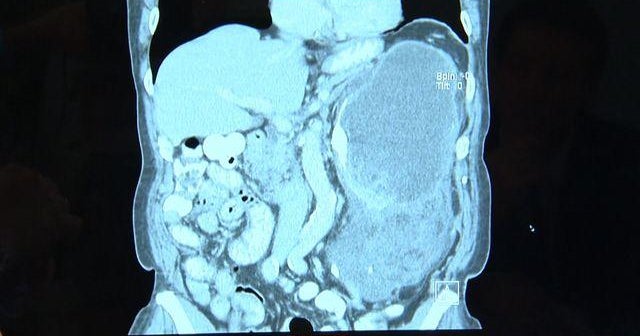

Doctors at NYU Langone Medical Center saved a man with a liposarcoma, a rare cancer. The patient had a 20-pound tumor and didn’t even know it. Craig Boswell reports this story from Staten Island, New York.